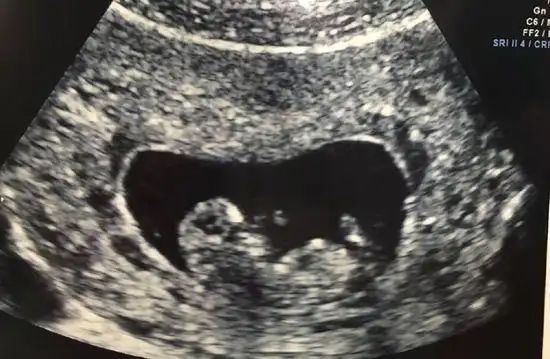

通常胎囊在5周出现,胎心在7周出现.

7月26日做的b超检查证实欢欢怀孕了,胚胎长3.4厘米.